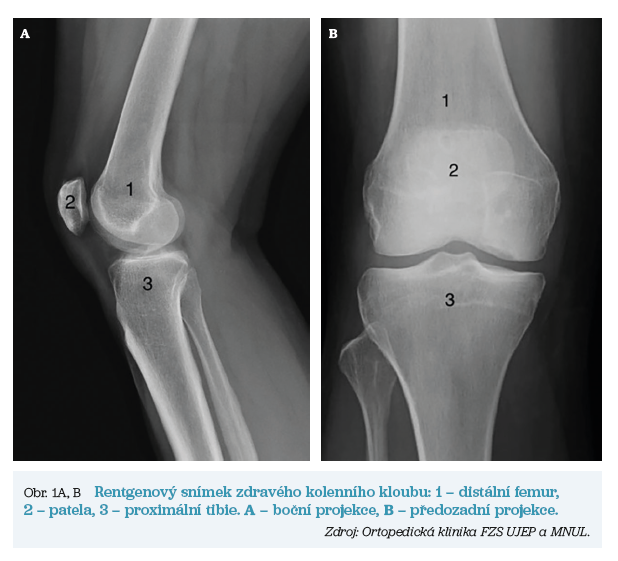

V obou případech však dochází k postupnému opotřebení kloubní chrupavky, ke zužování kloubní štěrbiny, tvorbě kostních výrůstku (tzv. osteofytů) a v nejzazších fázích až k nekróze kostní tkáně. Pomocí rentgenových snímků lze tyto artrotické změny vizualizovat. Základní anatomii a rozdíly mezi zdravým kloubem a kloubem postiženým artrózou ukazují obrázky 1 a 2.

Při implantaci totální endoprotézy (TEP) kolenního kloubu jsou nahrazeny artikulační plochy distálního femuru, proximální tibie a případně i pately.